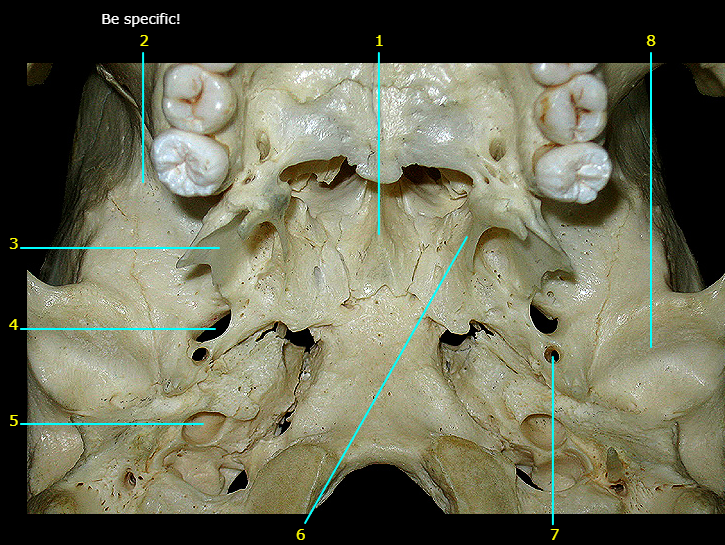

Choanae

Name #8

Ethmoid

Name #7

Sphenoid

Name #3

Lateral plate of pterygoid

Name #6

Medial plate of pterygoid

Name #5

Hard palate

Name #1

Maxilla

Name the bone

Palatine

Name the top structure

Greater palatine foramen

Name the bottom structure

Lesser palatine foramen